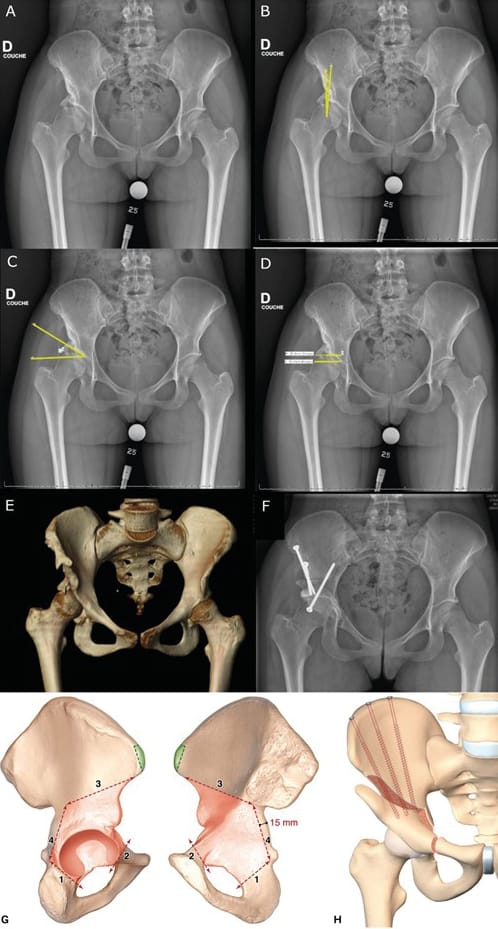

Bone block arthroplasty

First described by König in 1891, the bone block technique has been adapted and modified by countless authors with an arthroscopic technique recently presented [7], Chiron P, Laffosse JM, Bonnevialle N. Shelf arthroplasty by minimal invasive surgery: technique and results of 76 cases. Hip Int 2007;17 Suppl 5:S72-82. https://doi.org/10.5301/hip.2008.1488[8] Migaud H, Chantelot C, Giraud F, Fontaine C, Duquennoy A. Long-term survivorship of hip shelf arthroplasty and Chiari osteotomy in adults. Clin Orthop Relat Res. 2004 Jan;(418):81–6. https://doi.org/10.1097/00003086-200401000-00014. It involves grafting a fragment of cancellous-cortical bone to the anterosuperior part of the acetabulum to improve bone coverage.

In contrast to the PAO or RAO this strategy increases the size of the acetabulum, similarly to the Chiari osteotomy, which involves metaplasia of the of the capsule and labrum to create a fibrocartilaginous interposition graft.

There are countless options for the approach route, with Smith–Peterson typically being used, although the Hueter anterior approach, minimally invasive medial approach described by Chiron and the Thaunat arthroscopic approach are all possible. The bone graft is taken from the exopelvic part of the iliac crest, and its size is determined preoperatively based on the desired correction. An incision is made at the anterosuperior part of the acetabulum, flush with the capsule, so that the bone block can be placed against the capsule and is stable without fixation. The fragment is then impacted until it is fixed well and/or fixed with screws and/or a plate.

The main complications are lysis of the graft and non-union.

Results have been mixed with 46% survivorship without THA for Fawzy et al and 37% after 20 years in our facility. This is in contrast to Japanese studies with over 70% survivorship with 30 years of follow-up. These results are, however, difficult to compare to those of PAO or RAO because they are used in different populations. In the bone block studies, the largest portion of the population are patients with osteoarthritis, while the advent of modern pelvic osteotomies has been more recent, meaning patient selection has improved, and consequently so have the clinical results. If we look at bone block in the absence of osteoarthritis and subluxation, the survival rate is 81% after 21 years of follow-up [8] Migaud H, Chantelot C, Giraud F, Fontaine C, Duquennoy A. Long-term survivorship of hip shelf arthroplasty and Chiari osteotomy in adults. Clin Orthop Relat Res. 2004 Jan;(418):81–6. https://doi.org/10.1097/00003086-200401000-00014. However, this is a salvage strategy for extremely subluxed or even dislocated hips in which neither PAO nor RAO is possible, nor Chiari osteotomy in view of the risk of the line ending in the sacroiliac joint, preventing medialisation (Figure 6).